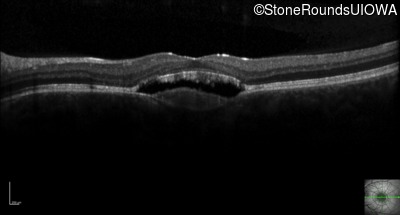

Optical Coherence Tomography - Left - 20/30 -1 sc

Exemplar / OCT Stack

OCT Stack